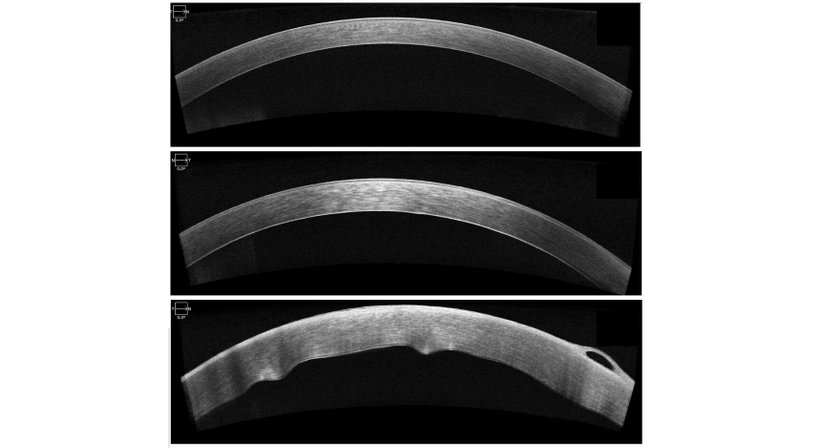

Hornhautnarben oder Unregelmäßigkeiten können ergänzend zur mikroskopischen Beurteilung am besten mittels hochauflösenden Laser-Schichtbildaufnahme (sog. OCT, optische Kohärenz Tomographie) untersucht und beurteilt werden. Auch dieses Messverfahren steht Ihnen in unserer Ordination zur Verfügung.